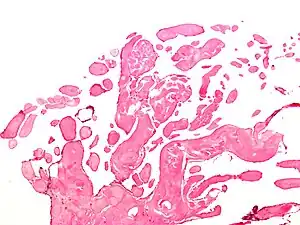

| Low magnification micrograph of an excised aortic valve papillary fibroelastoma showing the characteristic avascular branching papillae, H&E stain | |

Papillary fibroelastoma are typically found and accurately diagnosed by imaging. The diagnosis is confirmed by pathology. Histologically, papillary fibroelastomas have branching avascular papillae, composed of collagen, that are covered by endothelium.